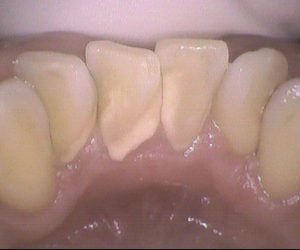

今日のクリーニングです。 クリーニング前 クリーニング後 下の前歯と上の前歯の裏側の写真です。 ステインがとてもつきやすく、3ヵ月毎にクリーニングにいらしています。 ステインに加 […]